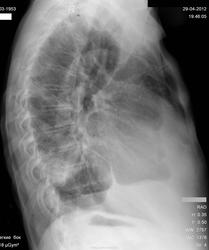

Справа, по-моему мнению, участок хорошего фиброза, возможно, за счет ТЭЛА сегментарных ветвей (старые). Все изменения связаны с сердечными проблемами. В жидкости справа не уверен, кажется плевральные наложения. Но если поставить УЗ датчик все сомнения исчезнут. Корни расширены. Сердце увеличено в размерах. И, вроде, имеется веретенообразное расширение грудной аорты.

Сердце не в норме: увеличение левого предсердия, увеличение правого желудочка, признаки лёгочной гипертензии. Но есть и уменьшение объёма нижней доли правого лёгкого либо её базальных сегментов. При этом воспаление в S9, S10 не исключается, возможно и не банальное, а как проявление инфаркт-пневмонии. Выпота немного: в синусах, над диафрагмой, паракостально. Осумкован и явно не сердечный транссудат.

Клиника нужна и томография нижней доли в боковой проекции.

Справа в плевральной полости есть выпот, он не свеж, он был и ранее. Межреберные промежутки справа, по сравнению с левой стороной сужены?

При таком выпоте не визуализируется главная междолевая щель - нонсенс? Или она превратилась в ту "закорючку", что располагается намного ниже и сзади?

По всей видимости, есть признаки уменьшения нижней доли справа в объёеме - цирротическая трансформация, или что другое?